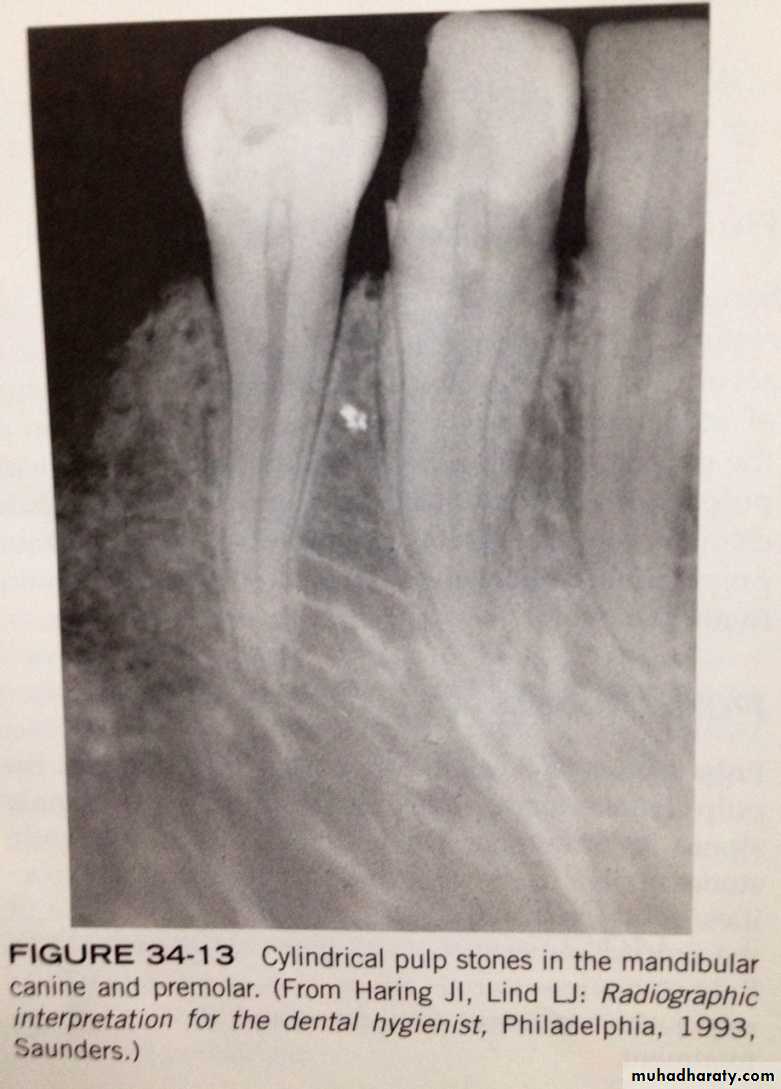

pulp stones- are calcifications that are found in pulp chamber or pulp canal. the cause unknown.

- On dental radiograph: pulp stone appear as round, ovoid or cylindrical radiopacities. do not cause symptoms and do not require treatment.

pulp stones